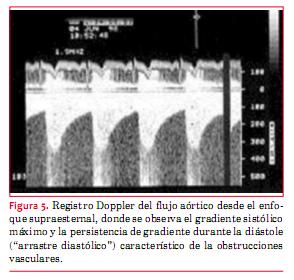

En la coartación de aorta (CoAo) posductal la morfología de la aorta es anormal en forma de S, como puede apreciarse en la figura 4. A este nivel suele observarse flujo turbulento con velocidad aumentada y gradiente que persiste en diástole (“arrastre diastólico”) (figura 5). Finalmente la aorta abdominal carece de expansión sistólica y de flujo pulsátil, registrándose, en cambio, flujo continuo (figura 6). La magnitud del gradiente registrado depende de la importancia de la coartación pero también de la magnitud de la circulación colateral que se haya desarrollado. Un gradiente sistólico máximo de 20 mmHg o superior se considera indicación para actuar sobre la misma (nivel de evidencia C)(15).